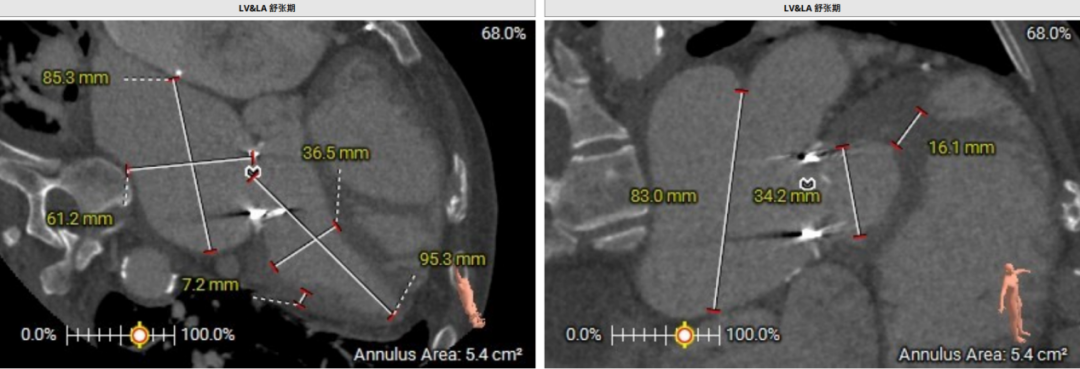

术前CT评估示:患者二尖瓣生物瓣置换术后,原生物瓣型号未知,生物瓣金属环平均内径25.9mm,外径31.5mm,瓣架高度15.9mm;

左室大小:95.3*36.5*34.2mm;

模拟27mm瓣膜植入情况: